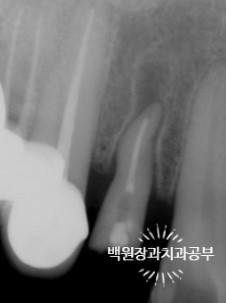

왼쪽이 외과적 정출술을 마친 직후에 찍은 치근단 엑스레이 사진입니다.

잘 보시면 치아가 자기 자리에서 빠져나와 보다 튀어나와 있음을 관찰 할 수 있죠.

오른쪽이 신경치료와 기둥 식립 그리고 크라운을 접착한 뒤의 엑스레이 사진입니다.

기존에 치아가 위치하고 있다가 빠져나온 자리는 이제 치조골로 채워져서 방사선상에서도 구별하기가 어려워졌어요!!